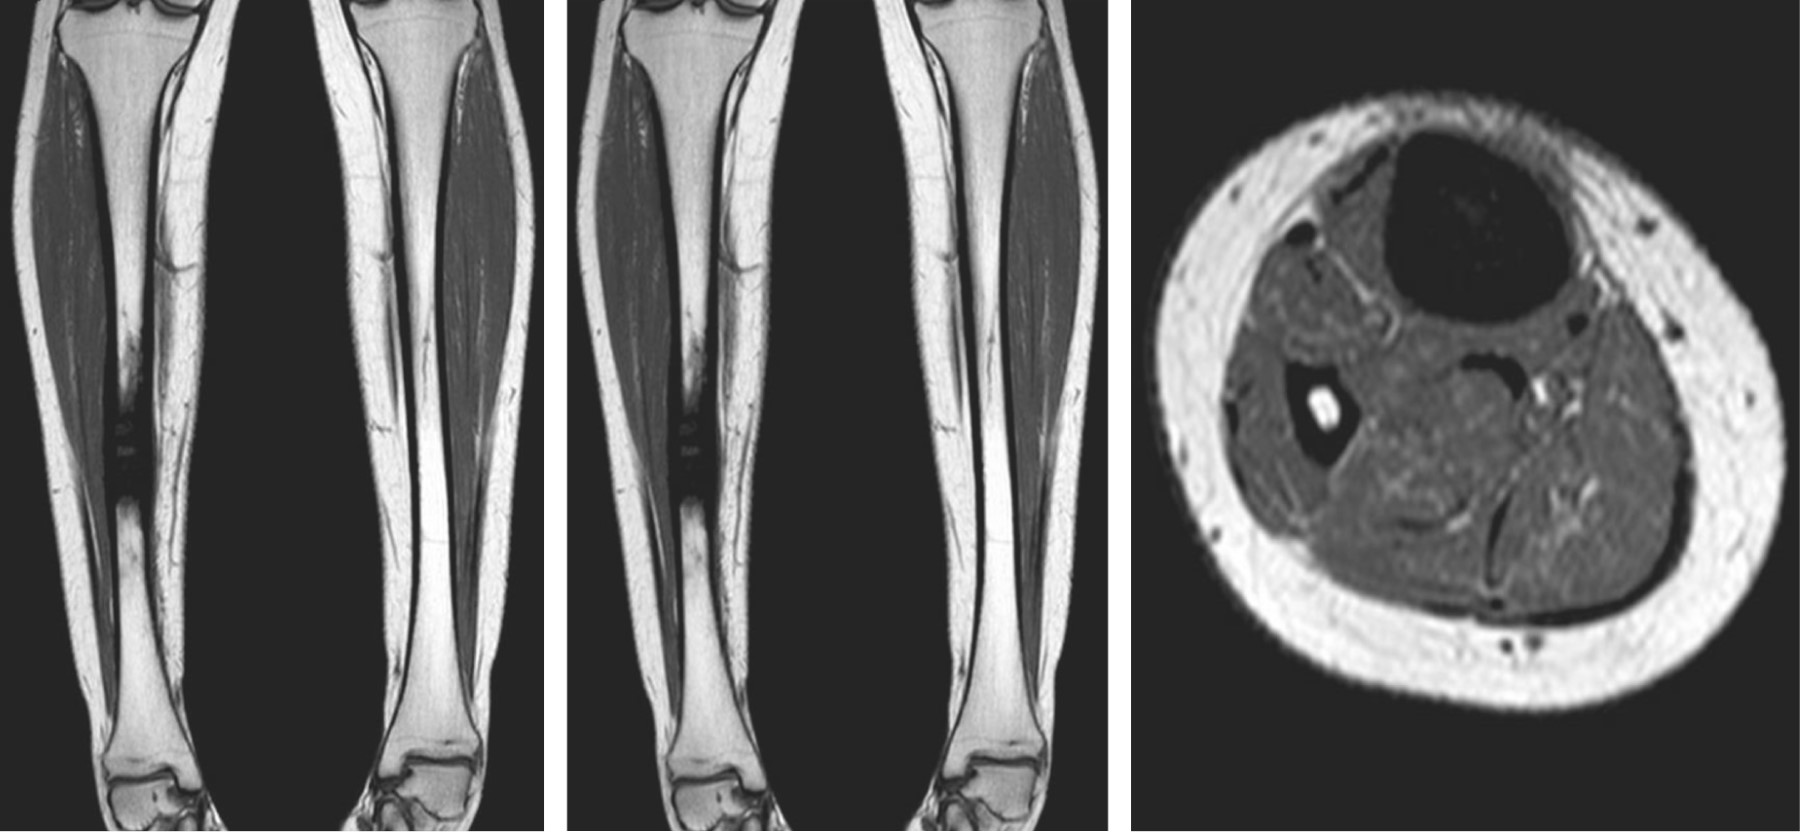

Se realizaron radiografías que demostraron una lesión intraósea diafisiaria única, de localización central, con bordes definidos, periostio engrosado pero sin interrupción y sin signos de malignidad. No se observó afectación de los tejidos blandos ni destrucción ósea adyacente (Figura 1). La resonancia magnética confirmó los hallazgos descritos; la lesión se caracterizó como inespecífica, con apariencia esclerosa y ocupación de toda la cavidad medular, con engrosamiento de ambas corticales (Figura 2). Se realizó una gammagrafía ósea que demostró una posible reacción osteogénica avanzada con evidencia de patología inflamatoria secundaria a destrucción ósea. Se realizó una biopsia incisional cerrada, que descartó lesiones infecciosas o neoplásicas.

El diagnóstico de la enfermedad se realiza mediante radiografía simple, tomografía, resonancia magnética, gammagrafía ósea y biopsia, excluyendo otras posibles condiciones. En las pruebas de imagen se observa un engrosamiento cortical de la diáfisis de los huesos largos y, en ocasiones, un estrechamiento del canal medular. La resonancia magnética confirma la presencia de esclerosis y revela edema de la médula ósea en la diáfisis.3 La gammagrafía ósea es útil para determinar la extensión de la enfermedad y para planificar la obtención de muestras de tejido. La biopsia puede ayudar en el diagnóstico diferencial y mostrar actividad histológica osteoblástica.

Figura 1